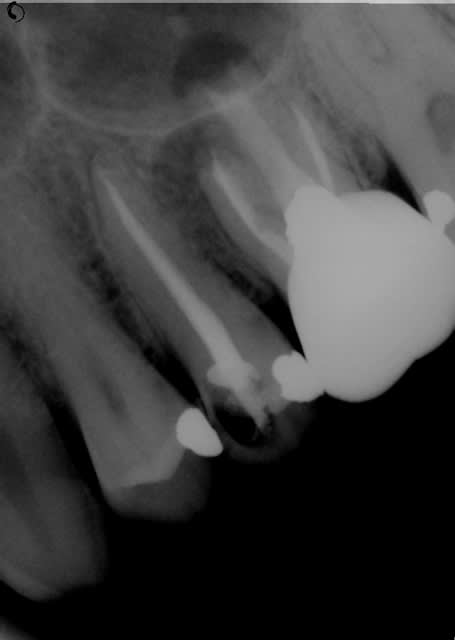

Patient 22-23 ans, endo de la molaire faite lorsqu'il avait 8-10 ans d'après lui.

Que faire sur un truc pareil?

Sauf que l'image apicale sur la racine MV pourrait indiquer une fêlure. Je déposerai déjà la couronne, sondage en mésial, observation au MO (ou loupe si tu as) avant de bloquer plus de temps pour rien.

Si tout semble ok, MTA dans le palatin.

A mon sens faire traiter la dent par un endo exclusif et la couronner par la suite, ça se tente mais c'est quand même pas mal risqué, d'une part au niveau de l'endo, le résultat n'est pas garanti (même si c'est toujours le cas...), et puis la racine palatine semble faiblarde, donc avec un tenon dedans, c'est pas dit qu'elle tienne super longtemps. De plus le coup pour le patient va être relativement élevé, alors qu'avec un implant, le pronostic est quand même plus sûr.

Sinon, si pas de fêlure, MTA pour le platin et vérifier le MV2 pour la racine MV.

Effectivement, bouchon de MTA sur la racine palatine.

Pour ce faire, desobturation complete, irrigation +++

mettre le porte MTA dans le canal et faire une radiographie de controle. L'embout doit descendre à environ 2mm de l'apex radiographique.

Si c'est bon, tu mets un stop en sillicone pour repérer la longueur.

Séchage du canal, et mise en place du MTA : il faut le déposer dans le canal sans pousser.

Radio de controle.

S'il est bien placé, avec des cones de papier de gros diamètre utilsiés à l'envers, tu ne foules pas le matériau, mais tu absorbes l'eau en excès.

Ensuite tu apportes du MTA jusqu'à obtenir une obturation apicalede 5 mm au minimum.

Obtruation du reste du canal à la gutta dans une seconde séance.

Ce n'est pas iumpossible sans microscope. Des loupes sont les bienvenues, et de toute facon faciliteront largement la procédure.

Je ne partage pas du tout ton avis. Réaliser un bouchon de MTA dense et étanche sur cette racine palatine est extrêmement difficile.

Ridicule de tenter ça sans microscope, et assez illusoire même avec. Il faut déjà retirer toute la merde du canal, et tant qu'à rien y voir, tu peux aussi travailler avec des gants de boxe.